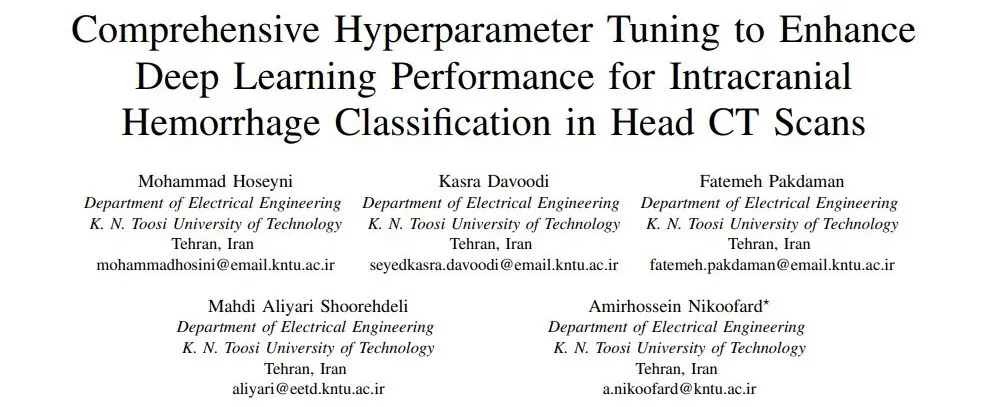

Publications

For more details click on the publication